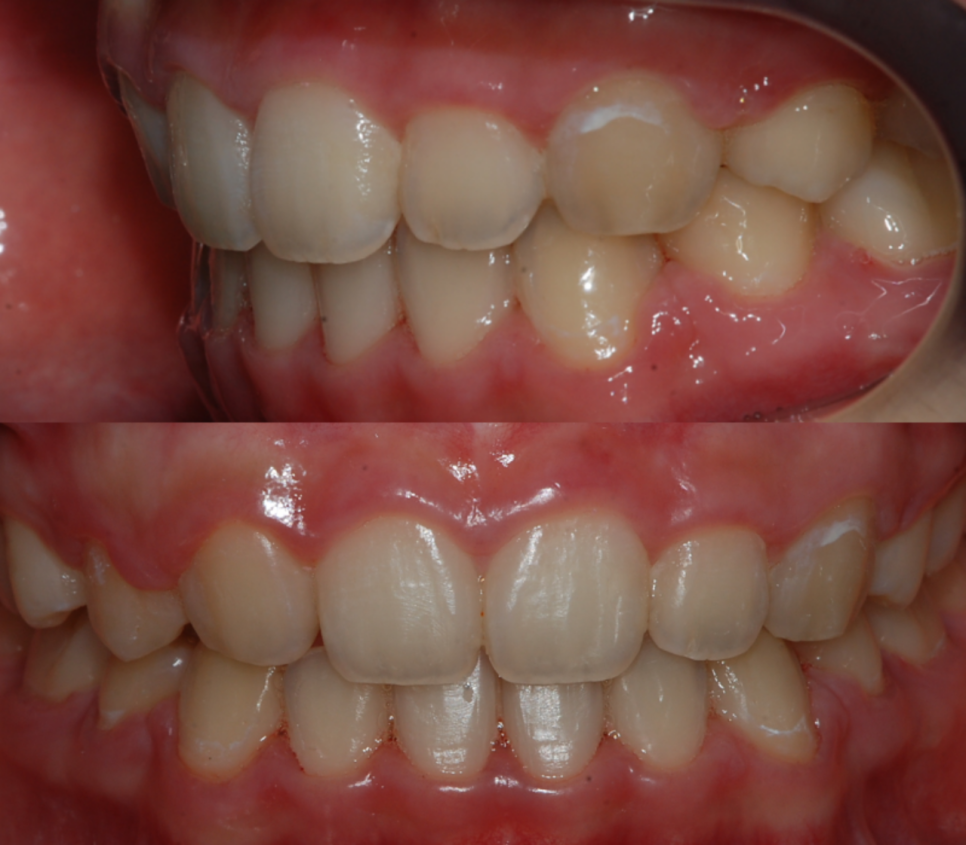

부정교합이 개선된 모습

바로 뻐드렁니교정 후 사진을

함께 확인해 보겠습니다.

위 사진을 보시면 교정 전 모습과 달리

앞으로 심하게 돌출됐었던 상악의 치아들이

후방으로 이동 후 가지런히 정돈되어

하악 영구치와 교합이 잘 맞물리는 것을

쉽게 확인하실 수 있는데요.

교정 종결 후 돌출 입이 해결된 모습

상, 하악의 부정교합이 개선된 덕분에

심미적으로도 보기가 좋지 않았던

사례자분의 콤플렉스 또한 해결되어

측면에서 보았을 때 더욱 심했던

돌출입이 확연히 개선되었답니다.

뻐드렁니 개선 전/후